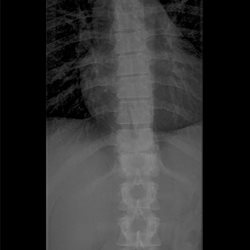

Thoracic Spine Plain Film 2